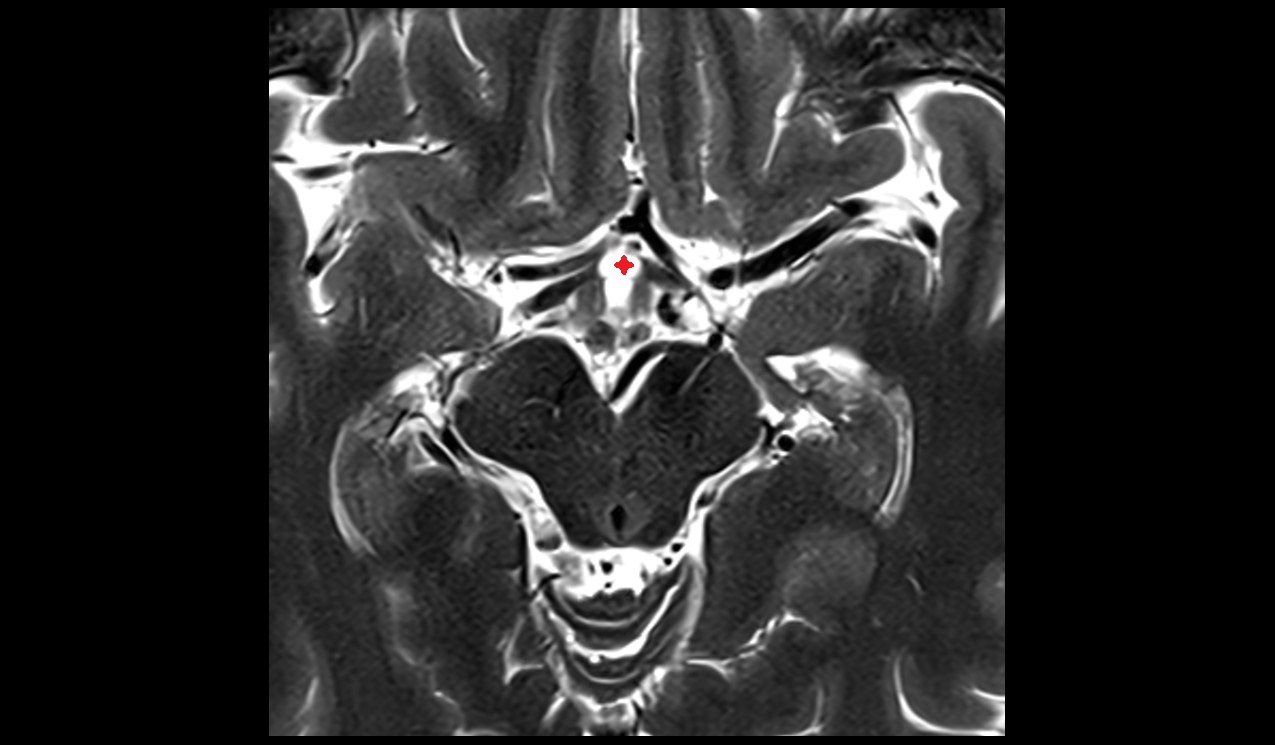

- Interpeduncular Cistern